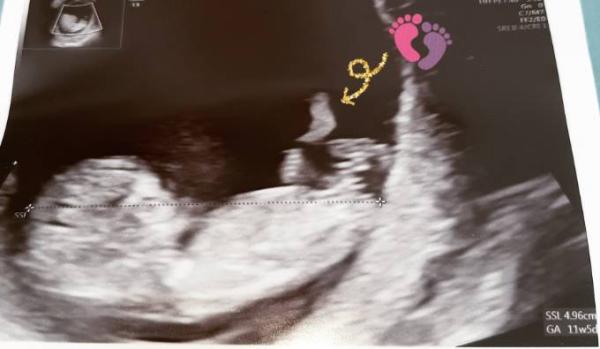

Wir sind auch fertig beim Arzt. 4,96 cm.. wow ein 5 cm Baby aktuell bei 11+2, Ultraschall sagt 11+5 aber wir belassen es beim 04.04.2020 Mein Blutdruck ist perfekt, mein Eisenwert auch, das war in der letzten ss nicht.. man hat das Gehirn schon deutlich gesehen und gestrampelt hat das kleine. So wunderbar dann hat es uns noch ein kleinen Fuß gezeigt. Wir sind so verliebt. Am 26.9 geht es dann zum ersttrimester Screening.. Bisher läuft alles wie es soll, ich bin so glücklich, da verfliegen die Sorgen.

Bild zu Ich bin verliebt < 3 FA termin. - Forum für April - Mamis